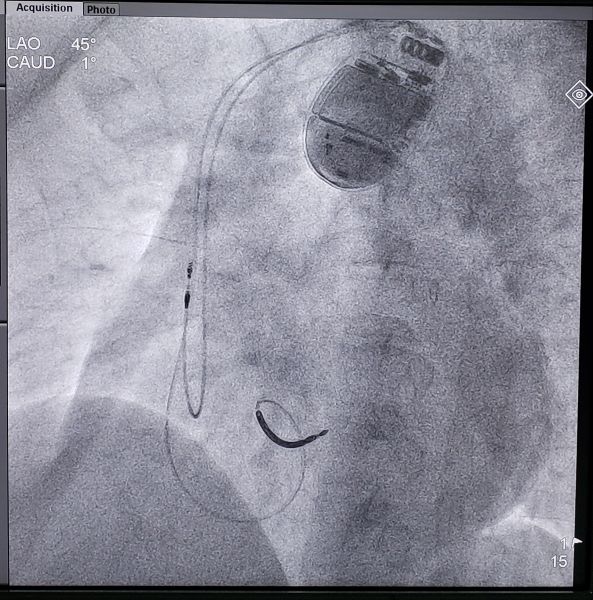

图为患者植入的兼容核磁共振双腔ICD及术后影像

12月27日,我院心内二科罗亚雄副主任等为一名患者植入一台兼容核磁共振的双腔心律转复除颤器(ICD),手术全程耗时仅60分钟,术中测试各参数良好,手术顺利完成。据了解,这是我省首台兼容磁共振的双腔ICD植入。

患者为一名51岁男性,因心力衰竭入院,经临床、心脏彩超和心脏磁共振等检查,诊断为肥厚型心肌病,患者同时合并心脏射血分数降低,而且有家族猝死病史,家族成员已有多人发生猝死。患者此次住院期间动态心电图显示有频发室性早搏和短阵室速,达到ICD植入1.5级预防指征,需植入ICD。考虑到患者相对年轻,心脏病变或其他病情今后还可能需要行核磁共振检查,建议患者植入兼容核磁共振的ICD。经反复与患者和家属沟通,患者选择植入雅培兼容核磁共振双腔ICD(Ellipse CD 2377-36QC)。

据心内二科王福军主任介绍,我国每年死于心脏性猝死的人数高达54.4万,而植入式ICD的植入是目前预防心脏性猝死最为有效的手段。这次由罗亚雄副主任主刀完成的我省第一台兼容核磁共振双腔ICD有以下特点:1.支持全身核磁兼容,安心磁共振检查;2.增加心腔突发性及远场形态学,大大降低误放电;3.增加ST段监测,提早发现心肌梗死;4.生理性外形、体积小、厚度薄、质量轻。这类新型ICD的临床应用,将给患者带来更多更实际的益处。